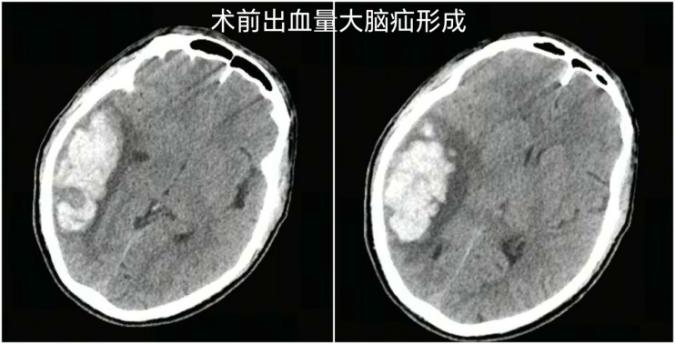

据南科大医院神经外科鲁春鹤主任介绍,患者当时右侧顶枕颞叶脑出血量高达约 40 mL,右侧大脑半球脑水肿、大脑镰下疝接踵而至,生命体征急速恶化,大脑里破裂的血管如同随时可能引爆的「定时炸弹」,情况岌岌可危。